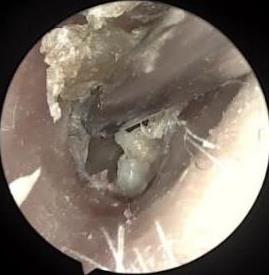

• 耳内镜下耳屏软骨-软骨膜鼓膜修补术后的短期疗效观察

摘要:目的 探讨耳内镜下耳屏软骨-软骨膜鼓膜修补术后的短期疗效。方法 回顾性分析2019年9月-2022年8月该院收治的78例鼓膜穿孔患者的临床资料,患者均采用耳内镜下鼓膜修补术。术后随访3个月,观察鼓膜形态和穿孔愈合情况,记录内镜图像、干耳时间、术前术后听力及耳鸣情况,以及外耳道狭窄等并发症的发生率。结果 术后3个月,鼓膜穿孔愈合率为97.44%(76/78),愈合良好,平均气导听阈较术前明显改善,气骨导间距较术前明显缩小,耳鸣较术前明显改善,差异均有统计学意义(P<0.05)。干耳时间为(4.21±1.12)周。术后出现肉芽5例,再穿孔2例,真菌感染2例,术腔感染、耳屏感染、外耳道狭窄和切口瘢痕各1例,所有患者术后均未发生面神经麻痹和感音神经性聋等严重并发症。结论 耳内镜下耳屏软骨-软骨膜鼓膜修补术是一种安全、有效的手术方法。根据术后愈合规律、内镜下鼓膜和外耳道形态特征,可为鼓膜修补术后正常中耳转归和并发症的诊疗,提供临床参考。